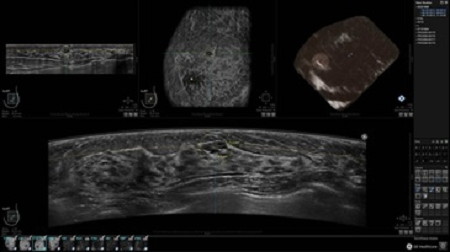

УЗИ-аппарат GE INVENIA ABUS позволяет проводить максимально операторонезависимые процедуры, что значительно снижает риск неправильной постановки диагноза и сопутствующие издержки на обработку информации. Система готовит отчет в течение 3-х минут после сканирования, это безусловное преимущество по сравнению с обычным УЗИ сканером.

• Получение объемных 3D изображений с возможностью покадрового просмотра

• Алгоритмы обработки изображений: алгоритм однородности изображения ткани (TEA), подавление зернистости, компенсация акустической тени от соска (NSC), определение границ молочной железы (BBD), определение стенки грудной клетки

• Отображение объемных 3D ультразвуковых изображений, которые состоят из традиционных поперечных и воссозданных коронарных и сагиттальных проекций

• Возможность отображения полного 3D изображения

Отображение и навигация

• Стандартизованная ориентация изображения: «толстый срез» в коронарной плоскости; поперечная; сагиттальная плоскость; радиальный и антирадиальный поворот изображения; просмотр исключительно области интереса

• 360 ° APC - отображение области по «любой точке компаса»